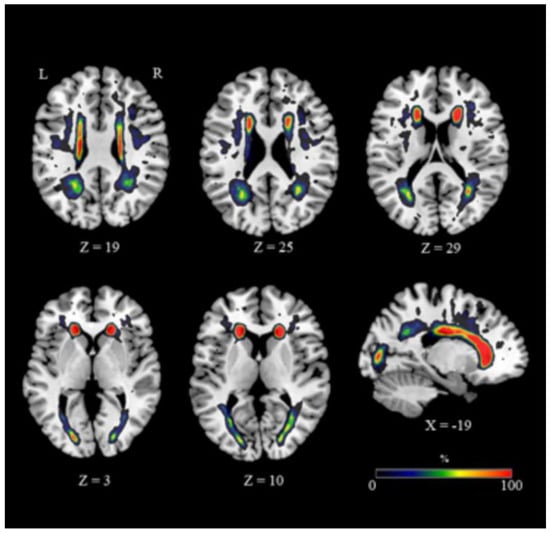

The extent and distribution of WMH varied considerably (Figure 1; mean volume ± SD = 7.869 ± 9.096 mm3, range 919–36.539) (Table 4). Anatomical WMH overlap maps were superimposed on the ICBM-DTI-81 white matter labels atlas [76]. Most of the altered voxels, indicative of undergoing damage, were localized in frontal areas, the anterior and superior corona radiata and the genu and body of the corpus callosum (CC) (Figure 1). More posterior regions were minimally affected by WMH (Figure 1).

Figure 1.

WMH distribution. Representative slices showing an overlapping of WMH maps. The color bar indicates the percentage of subjects overlapping obtained for each voxel. Legend: R, right; L, left; Coordinates are in Montreal Neurological Institute (MNI) space.